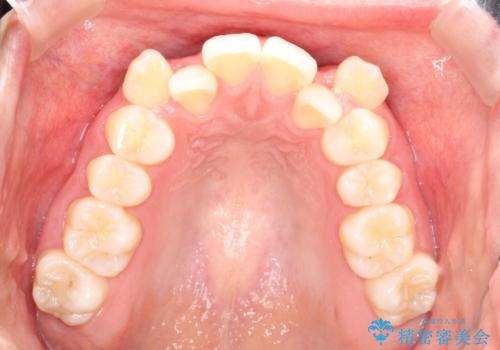

重度のガタガタ ハーフリンガルによる目立たない抜歯矯正

- 八重歯と前歯のガタガタを主訴に来院されました。

目立たない装置をご希望でしたので、上下左右の歯を1本ずつ抜歯してハーフリンガルでの矯正を行いました。